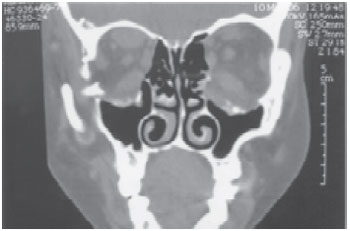

Tendo em vista a exposição crônica do globo ocular, o longo período de evolução e o comprometimento da estética facial com suas repercussões psicossociais, optamos pelo tratamento cirúrgico expansivo / descompressivo de órbita e reconstrução palpebral. Foram realizados cortes tomográficos pré-operatórios para avaliação inicial da morfologia orbitária (Figura 2).

Figura 2 - Corte tomográfico coronal pré-operatório, mostrando o excesso de gordura intra-orbitária, causa da pressão sobre as pálpebras.